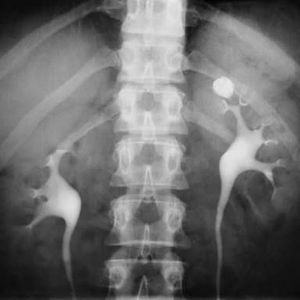

Diagnosis?

Kidney

X Ray

Ivu

Left renal stone

Renal stone

Calyceal stone ?